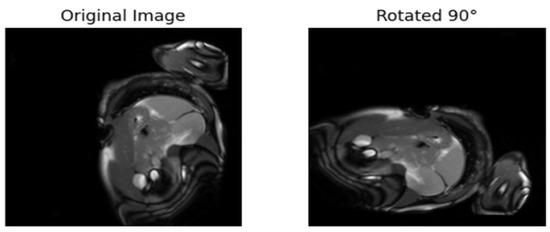

| [17] | Rotates the images 90°, 180°, etc. The model is trained to predict the rotation. | Labels are from the rotated angles |